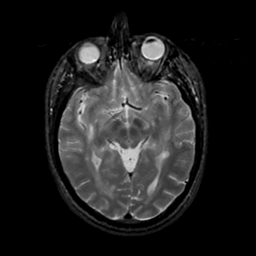

MR Study #20 October 6, 1991 -- Slice #22